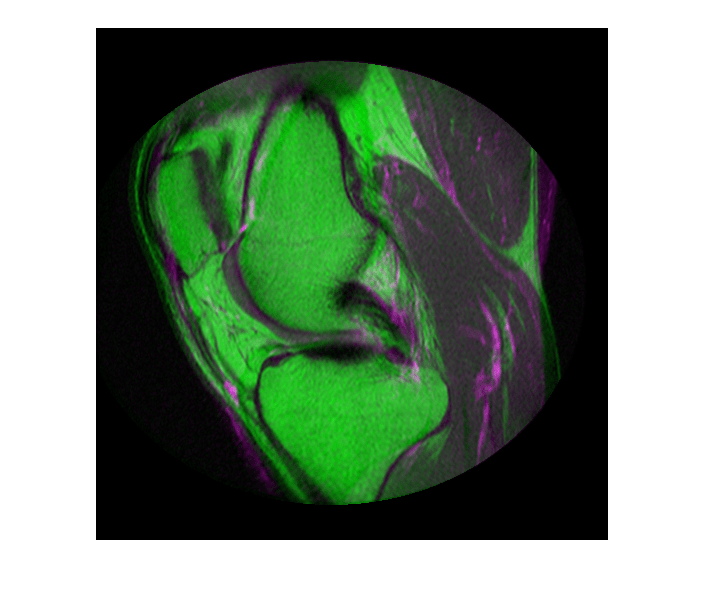

Считайте два изображения. Этот пример использует два магнитно-резонансных (МРТ) изображения колена. Фиксированное изображение является спин-эхо-изображением, в то время как движущееся изображение является спин-эхо-изображением с восстановлением инверсии. Два сагиттальных среза были получены одновременно, но немного не совпадают.

Просмотрите несовпадающие изображения.

imshowpair(fixed, moving,'Scaling','joint')

Просмотр зарегистрированных изображений.

figure

imshowpair(fixed, movingRegistered,'Scaling','joint')